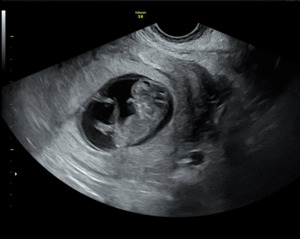

A formal transabdominal and transvaginal ultrasound subsequently revealed a viable intrauterine pregnancy consistent with 10 weeks gestation, confirming the diagnosis of a missed intrauterine pregnancy coexisting with a resolved EP: a HP. The fetus demonstrated appropriate growth and viability. The patient elected to continue the pregnancy and initiated prenatal care.